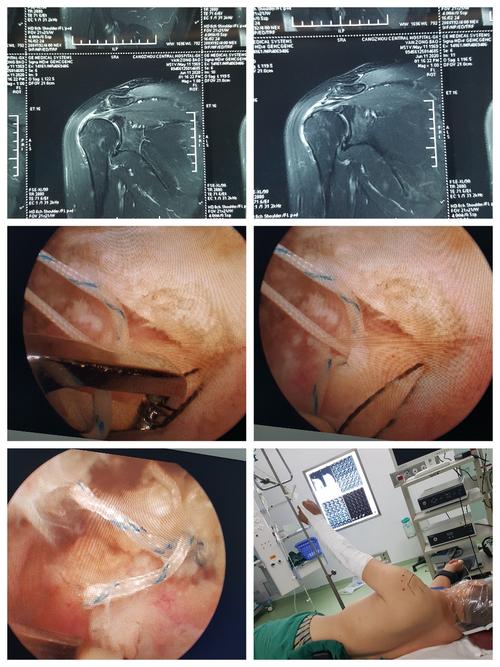

全镜下bankert修补 remplissage术(冈下肌关节囊填塞固定术)治疗复发

术中证实肩峰撞击综合征合并肩袖撕裂,关节镜下前建峰成型及肩袖缝合.